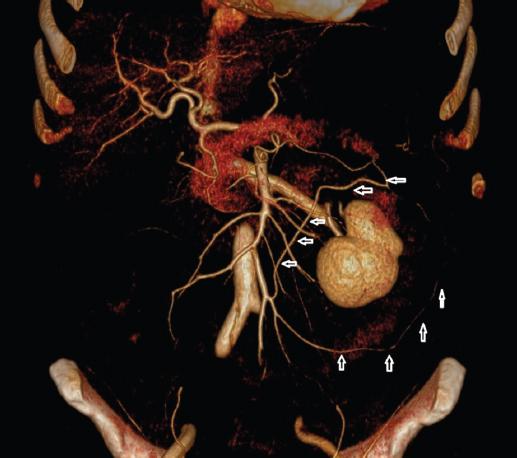

Marginal artery of Drummond is a collateral pathway that connects the SMA and IMA systems closest to the colon wall1. In our study, we found the presence of this artery in all 103 (100%) patients (Figs. 1-3).

Figure 1 Three dimensional-computed tomography angiography: Riolan’s arc (transverse arrows) and Drummond’s marginal artery (longitudinal arrows).

Riolan’s arch is an “intermediate” anastomosis between the branches of the SMA and IMA in the mesentery of the colon2,4. In our study, we found the presence of this structure in 47 (45.6%) patients (Figs. 1-3).